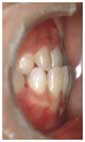

普通の前歯のかみ合わせ: |

人の歯は、上の前歯が大きく、下の前歯が小さくできています。このため、上の前歯が下の前歯の力を受けとめるのに都合が良くなっています。 |

| 上の前歯は下から突き上げてくる下の前歯の力に十分耐えるために、下の前歯に比べて、大きく、太くできています。 | ![]() |